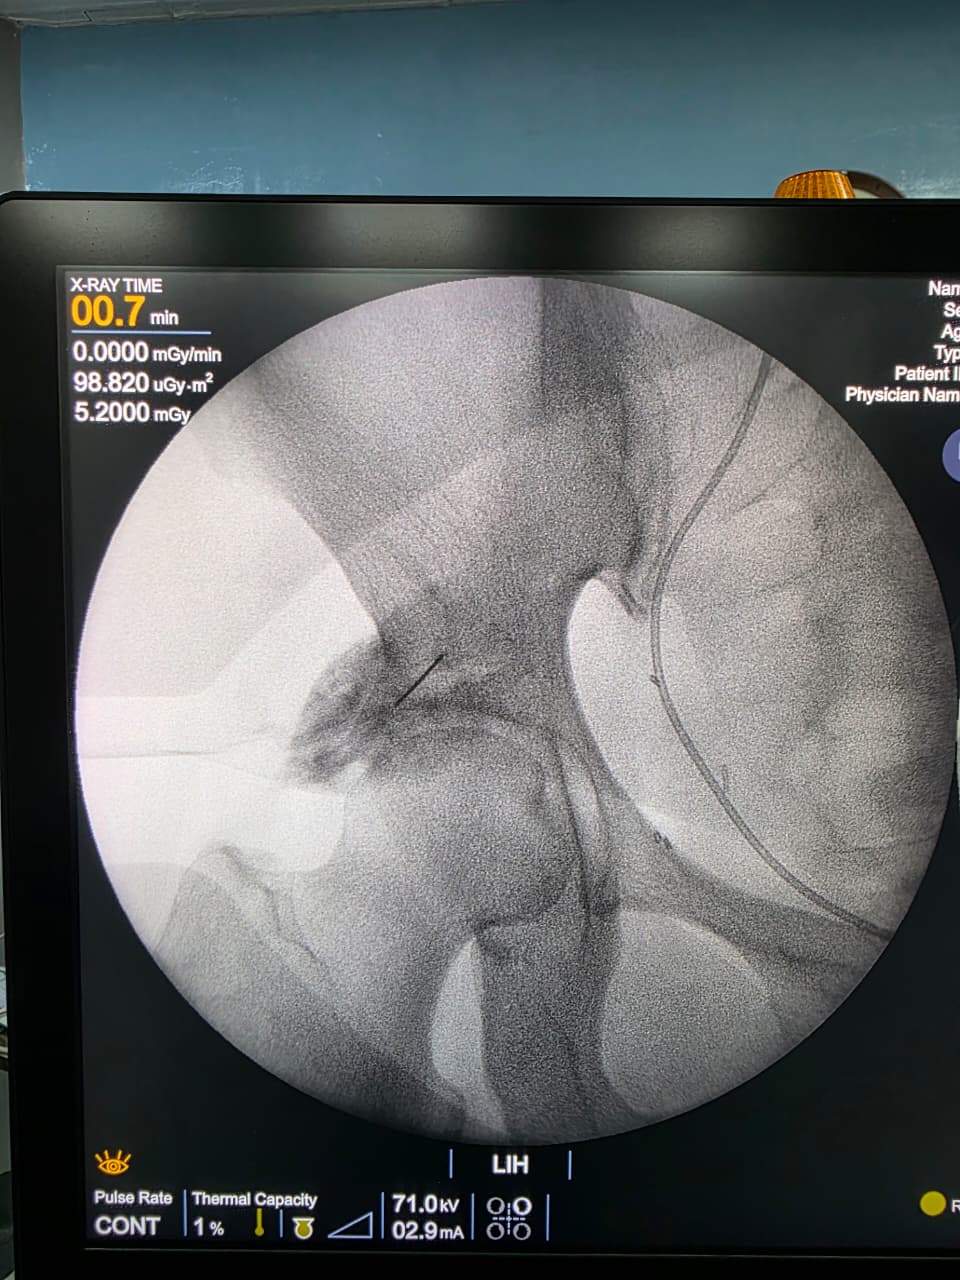

Procedures